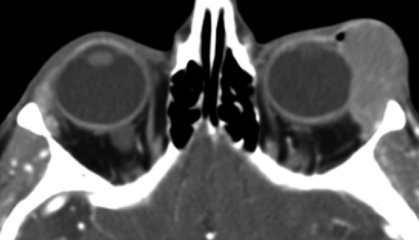

Dacryoadénite

- Inflammation / infection de la glande lacrymale

- Aigue: bactérienne, pseudotumeur

- Chronique: sjogren, vasculites, sarcoidose…